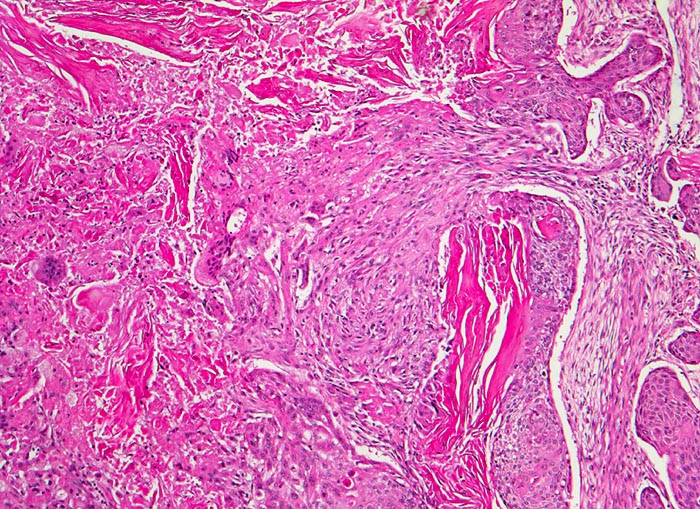

Verhornende Plattenepithelkarzinome sind charakterisiert durch mehr einzeln gelagerte Zellen mit deutlicher Pleomorphie, das Zytoplasma ist dicht und orangeophil. Die Kerne sind pyknotisch oder erinnern an Lavabrocken.

Die Abbildungen zeigen ein verhorntes und ein unverhorntes Plattenepithelkarzinom zum Vergleich.